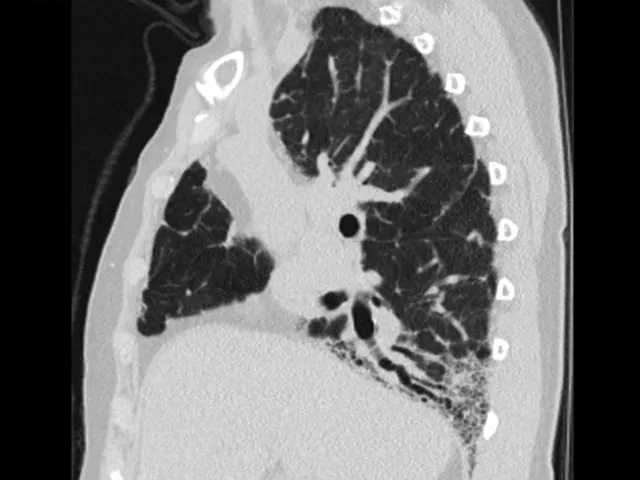

This Reporting Module is aimed at radiologists, pulmonologists, and rheumatologists who are interested in strengthening their clinical skills in the interpretation and identification of different patterns of interstitial lung disease with anonymized real scleroderma cases.

- To be able to identify and describe the various ILD patterns seen on Scleroderma scans